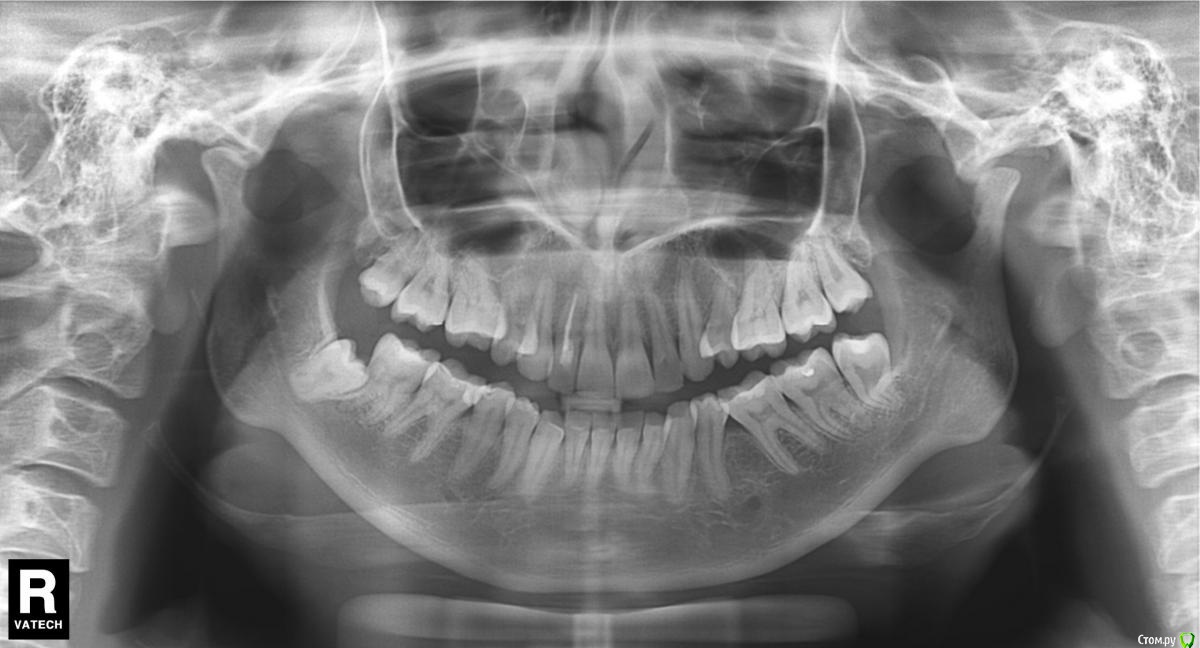

dianchik Опубликовано 16 февраля, 2016 Поделиться Опубликовано 16 февраля, 2016 Добрый день! Подскажите, пожалуйста, очень боюсь удалять зубы. Предыстория: с декабря 2015 возле 7ки снизу справа ближе к щеке немного отошла десна, туда стала попадать пища. Чищу монопучковой щёткой, но не уверена, что все прочищаю. В связи с этим обратилась к врачу. 2 стоматолога сказали удалить снизу 8ку непрорезавшуюся. Набравшись духа обратилась к хирургу. Его ответ был, что не стоит этого делать, пока не время. Говорит, что сидит глубоко, рядом нерв. Вообщем напугали до жути... С 15.02 начали на нижней челюстт немного болеть передние зубы. Как-будто верхушки зубов друг на друга давят, но так таковой боли не чувствую. Связано ли это с непрорезавшейся 8кой? И стоит ли удалять эту 8ку? (снимок как-будто перевернутый, то что слева на самом деле внутри справа) Ссылка на комментарий

Doctor Vlad Опубликовано 16 февраля, 2016 Поделиться Опубликовано 16 февраля, 2016 на сколько сложно это для кого? для всех по разному! зуб не простой но не критично. нерв может и не рядом но работать нужно так как будто ближе некуда! кт снимок лишним не бывает . пригодится на других зубах Ссылка на комментарий